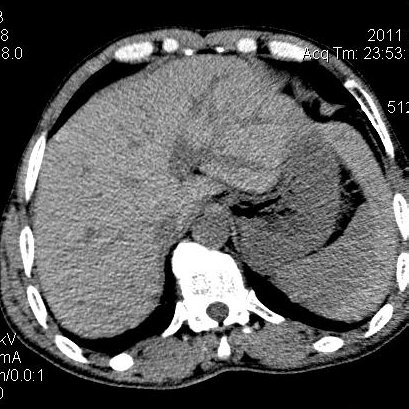

肝左叶发育异常

男性,55岁,骑摩托车摔倒后入院,自述右上腹疼痛

[backcolor=#FF0000]第一次诊断的时候也是这么肯定,可是床旁超声检查并没有发现明显异常,而且患者的一般症状都良好。还好临床只是保守治疗,没有立即手术,第二次复查的时候没有一点变化,又做了MRI检查,没有血肿,

这是一例肝左叶发育异常的,很个性吧~[/backcolor]